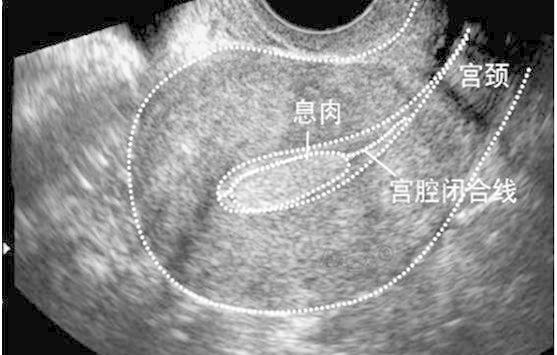

子宫内膜息肉

还有很多疾病超声显示子宫内膜回声不均,如苗勒氏管混合瘤、内膜损伤性改变(子宫内膜炎,宫腔黏连,瘢痕等)、滋养细胞疾病、间质细胞增生、子宫内膜结核等。

超声是妇产科的主要辅助检查手段,某些疾病的早期,在超声表现不典型,不可能替代病理,遇到超声提示:内膜回声不均时应该警惕以上情况的出现,可以诊断性刮宫送病理结 合宫腔镜检查还要结合临床及其他检查,进一步明确诊断。同时不要紧张,因为有一部分是正常的,如:药物流产后,子宫内膜没有来得及修复,这种情况是正常的,也可见于使⽤外源性雌激素药物等。